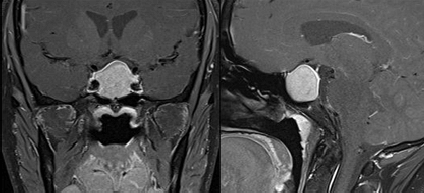

Case 1: 35/ M

- Pre-operative Coronal and Sagittal contrast enhanced T1W images show a well circumscribed homogenously enhancing sellar mass with suprasellar extension (Figure 1).

- Intra-operative coronal and sagittal T1W (Figure 2) contrast enhanced sequences show no residual enhancing tumour in the post operative bed (Figure 3).

Figure 1

Figure 2

Figure 3